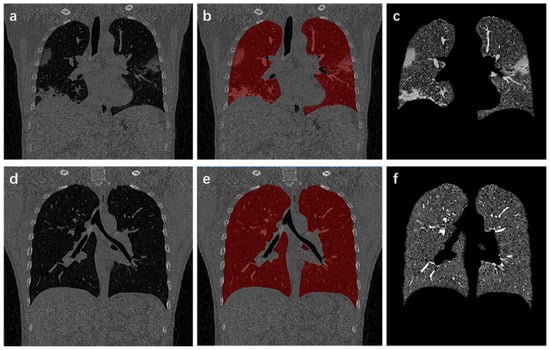

where x s and x u correspond to probabilities of marked and non-marked points, respectively. To obtain x u , differential of D [ x u ] with respect to x u is solved, and the extreme point through the zero point is found. L u x u = B T x s is satisfied after solving. x i s is supposed to represent probability that vertex v i belongs to label s. Set of s tags is defined as Q ( v j ) = s and v j U s , where 0 < s K and K is the number of all seed points. Thus, solution of Dirichlet problem is L U X = B T M . Segmentation result is obtained through this equation (Figure 3). For any vertex, the sum of all probabilities is 1. So s x i s = 1 , v i V is satisfied.

Figure 3. Process and results of lung region extraction. (a,d) are the original CT images; (b,e) show results of lung mask covering the original CT images; (c,f) indicate the extracted lung area.